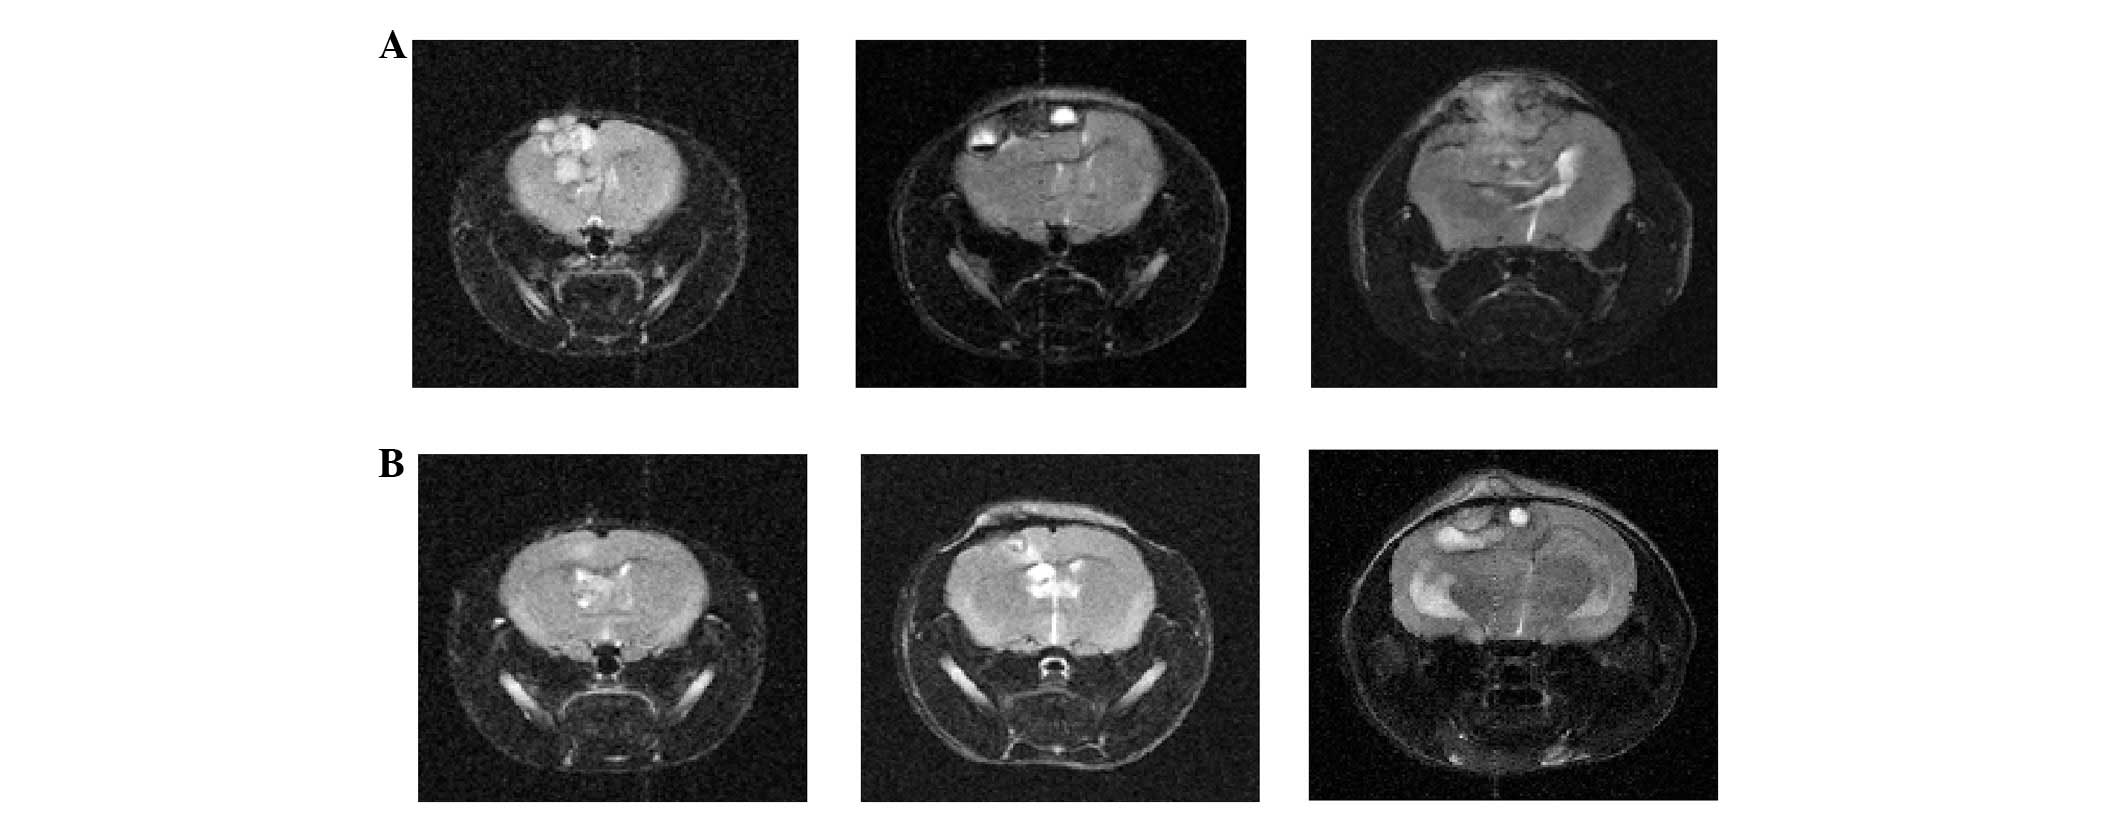

Activated astrocytes produce a wide variety of cytokines, including IL-1, IL-3, IL-6, TNF-α, TGF-β, IGF-1 and PDGF. Cytokines released by activated microglia include IL-1, IL-6, TNF-α, MCP-1, and MIP-1. IL-1, IL-3, IL-6, TNF-α, TGF-β, PDGF, MCP-1 and MIP-1 expression was higher in rapamycin-treated mice compared with controls (Fig. 3). IGF-1 expression, however, was lower in rapamycin-treated mice than control mice. Rapamycin treatment before tumor cell inoculation affected the later cytokine expression in the tumor. The tumor progressively increased in size, and compressed the brain parenchyma at 4, 8 and 12 weeks after inoculation in control mice. In mice treated with rapamycin before inoculation, the tumor formed and thrived slowly (Fig. 4).

Figure 4

Serial magnetic resonance imaging (MRI). (A) A tumor was noted in the cortex of the right hemisphere 4 weeks after intracranial inoculation of 1×106 NCI-H358 cells (left). The tumor size progressively increased and compressed the brain parenchyma at 8 weeks (middle) and 12 weeks (right) after the inoculation of control mice. (B) In mice treated with rapamycin before inoculation, the tumor formed and thrived relatively slowly. Left, 4 weeks; middle, 8 weeks; right, 12 weeks.